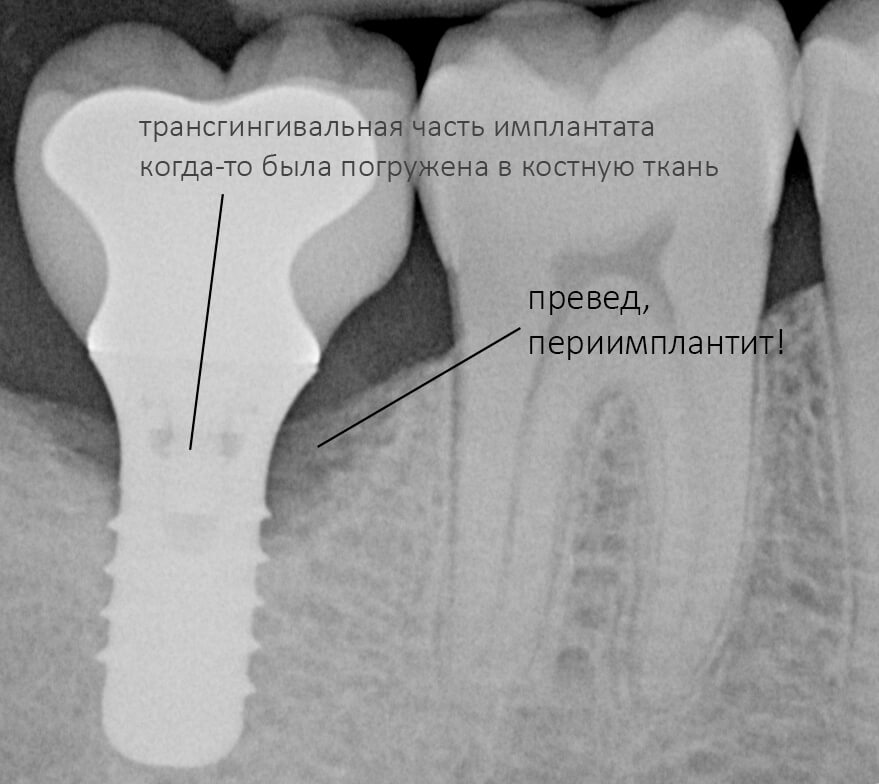

Рекомендации по установке имплантов. Для всех. Часть V.